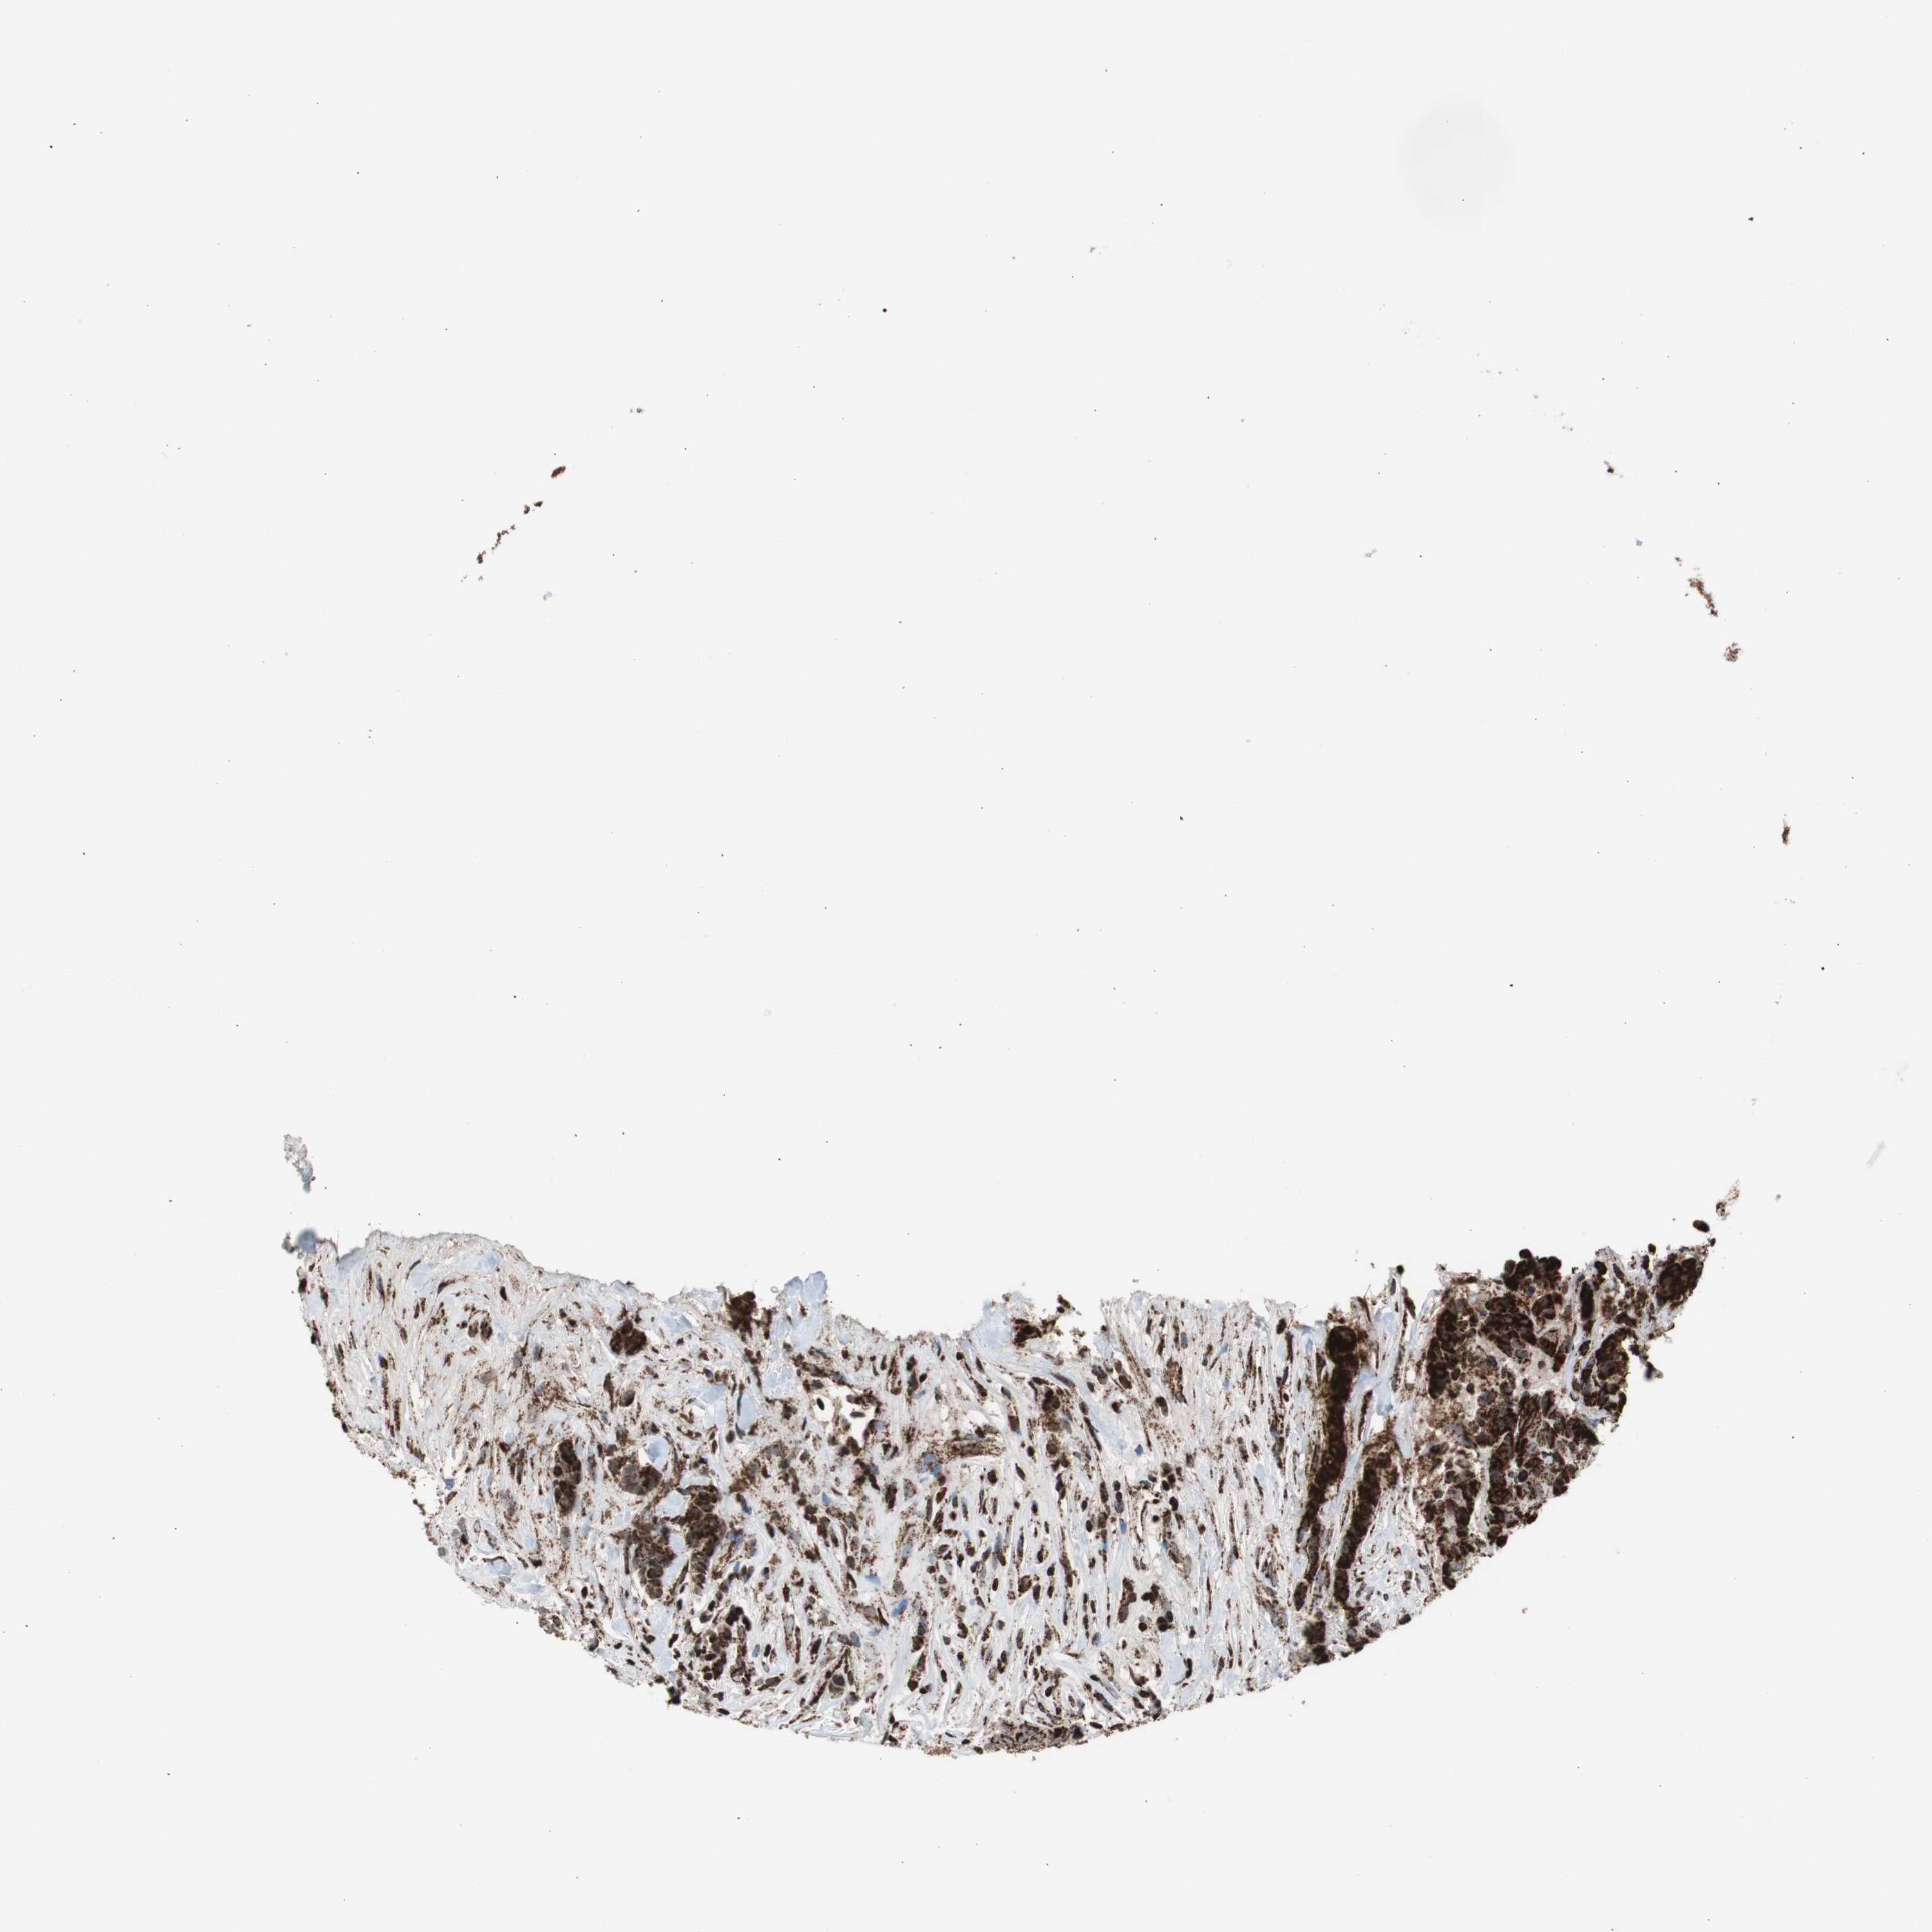

BRCA TCGA BRCA VALIDATION PROTEIN EXPRESSION

ANTIBODIES

AND

VALIDATION